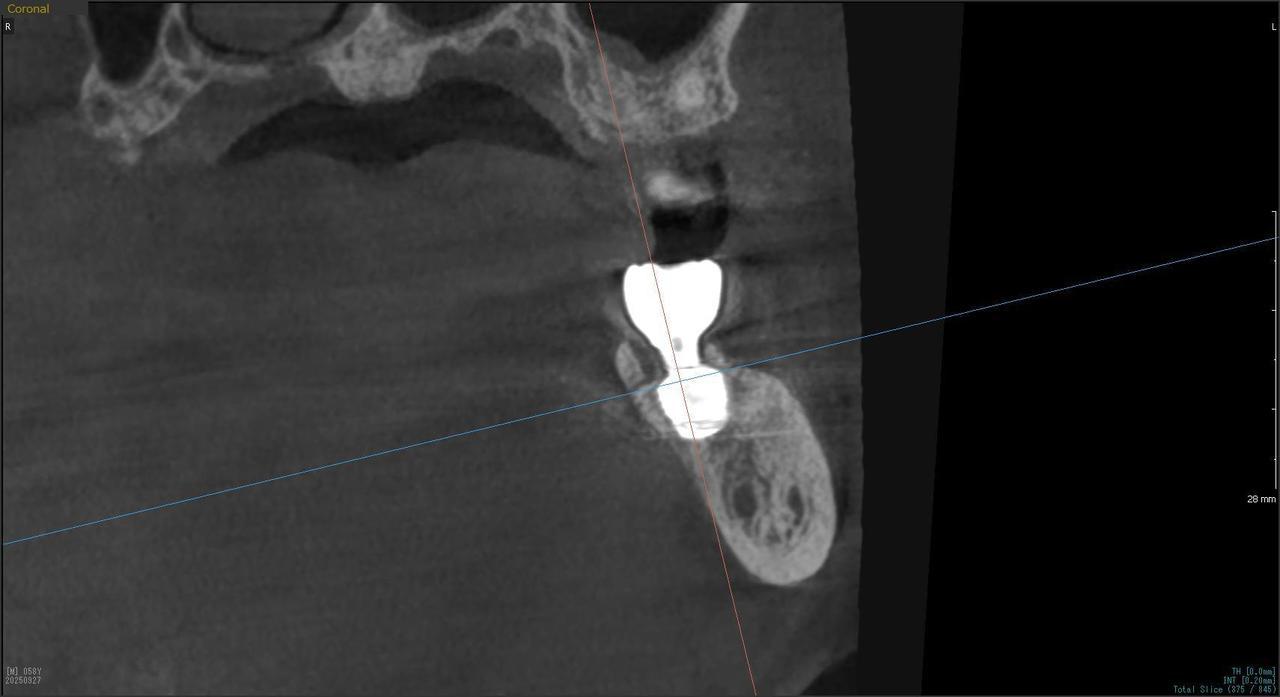

5.左上4番のインプラント抜歯即時埋入、左上6番の上顎既存骨1から2mmのグラフトレスサイナスリフト、左下56の大幅な骨欠損により、下顎神経の損傷を回避するために、ショートインプラントを使用し、左下56にインプラントを埋入し、最終補綴物は、左上456の3ユニットのジルコニアブリッジし、左下56は、ジルコニアの連結冠を装着したケース

M・I 様 女性 70代

症状としては、左下56は、歯周病で欠損したと考えられるが、かなりの骨欠損をともなっていた。左上456に関しては、動揺が大きく、炎症が起き、排膿、および、歯性上顎洞炎を起こしていた。

治療法としては、動揺がひどくなってきて、炎症の症状もあったため、左上56の抜歯を希望。インプラント治療をその後、希望したため、左上4に関しては抜歯即時埋入。左上6に関しては、既存骨1から2mmでインプラント治療が厳しい状態であったが、グラフトレスサイナスリフトを行い、治療期間5か月はかかるということを説明して、インプラント埋入をおこないました。その後、2か月半後、大幅に骨が欠損している下顎56に対して、ショートインプラントを使用して、下顎神経の損傷を避けて、インプラント埋入を終えています。その後2か月後に光学印象で印象を行い、上顎刺億456歯、3ユニットのジルコニアブリッジを装着。下顎左側56に関しては、骨欠損が大きいため、歯冠長がだいぶ長くなるため、ジルコニアの連結冠を装着して治療を終えた。

治療結果は、上顎6に関しては、既存骨が少なく、厳しい治療ではありましたが、5か月で治療を終え、患者様の負担を最小限に抑えるができたと考えます。(従来のサイナスリフトでは、このようなケースでは1年以上、1年程度の治療期間がかかるか、治療が不可能と言われるケースだと考えます。)また、下顎は骨欠損が大きく、下歯槽管のリスクが起きることが考えられますが、ショートインプラントを使用することで安全に治療を行うことができました。

治療の期間・回数:治療期間5か月(上顎456 3ピースブリッジの治療は5か月(上顎既存骨が2mm程度しかなく、骨結合に時間がかかるケースであったために、5か月の治療期間が必要であった。)(左下56に関しては2か月半で治療を終えています。)治療回数は、13回。